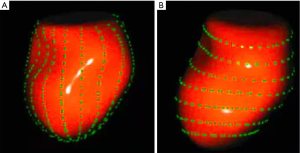

Principles of 4D Auto LAQ

A semi-automated segmentation algorithm was used for volume calculation. The algorithm was initialized with 1 landmark located in the center of the mitral valve (MV) at the annulus level. The segmentation algorithm computes the deformation of the 3D model by solving a state estimation problem using an extended Kalman filter that combines the LA motion model, geometry, and edge detection algorithms. Strain was calculated based on changes in the lengths of different lines along each anatomical direction. To calculate longitudinal strain, 8 longitudinal lines (Figure 1A), each connecting 2 opposite LA basal points, were sampled from an automatically constructed triangular mesh. To calculate circumferential strain, 7 circumferential lines (Figure 1B) that were equidistantly distributed between the LA base and the LA apex were used. The strain time was then calculated for each frame s(t) = (L(t) – L(tr))/L(tr) x 100%, in which L(t) is the line length at time t and tr is the time of the left ventricular end diastole (ED). Global strain was calculated as the average strain of the respective directional lines of each direction.